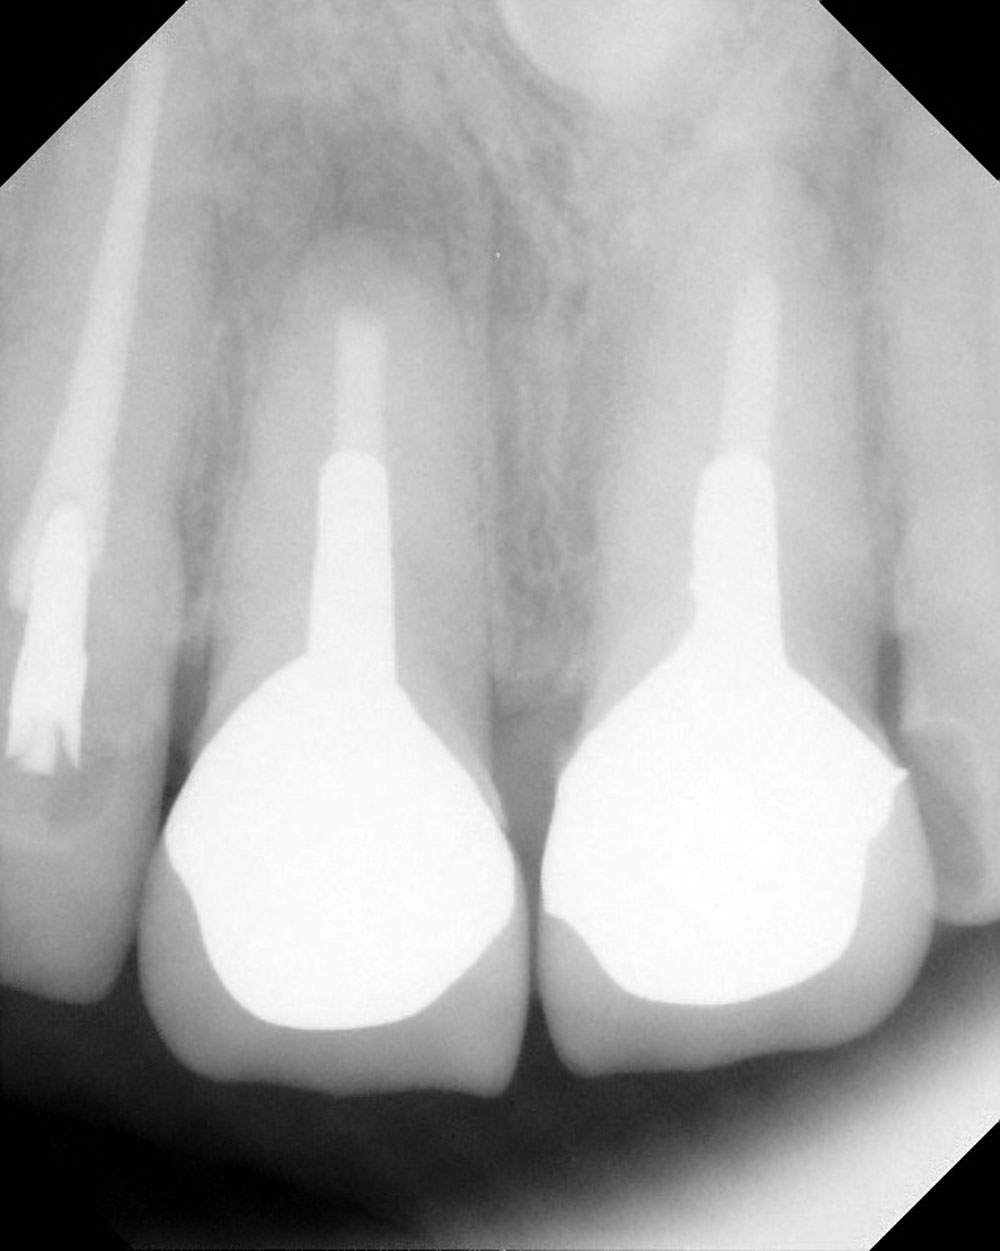

術前レントゲン写真

- デンタル(小さな部分レントゲン)術前所見―向かって左の一番前の歯(右上1番)根っこの先が黒くなっている骨透過像を呈する。

- 診断―歯根端切除予後不良による根尖性歯周炎の再発、クラックの疑い。